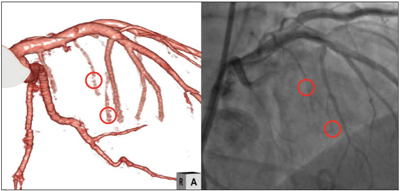

冠動脈における慢性完全閉塞(Chronic Total Occlusion:CTO)病変に対するCT画像の有用性に関してはいくつかの報告があり、その治療の難易度を評価する指標にも用いられる。しかし、カテーテル室で用いられる治療支援画像の条件としては、カテーテルによる造影画像と同じアングルで形態観察が可能でなければならない。われわれの施設では、Volume Rendering (VR)画像を用いた3DMAPを治療支援画像として提供している。これは、通常の造影された血管内腔のVR画像に閉塞血管の外観をフュージョンさせたもので、閉塞部分の血管形状や石灰化の分布などの把握が容易であるとともに、アンギオ装置のビューアングルに合わせた画像を簡単に表示可能なのも特徴である。さらに、最近では側副血行路を介して逆行性にガイドワイヤーを進める治療も行われるため、この方法が選択される場合には、側副血行路のルート検索が重要となる。CTで描出される側副血行路は、CT画像の空間分解能の限界もあり、比較的血管径の保たれたルートと考えられるため優先的に選択される。特に、中隔枝はその第一候補となるが、通常の閾値抽出によるVR画像では描出が困難なため、パスによる抽出も活用している。一部、マニュアル作業にはなるが、側副血行路の走行形態や本幹接続部位の把握に有効であり、その信頼性に関しては、CPR画像による連続性から確認できる(図2)。

図2 側副血行路の描出も含めたCTO病変の3DMAP画像

カテーテル治療時に用いられるビューアングルに合わせた画像を作成している。